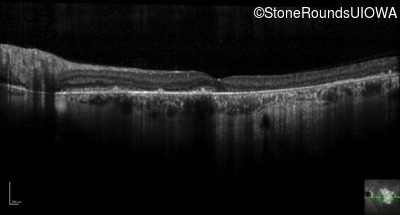

Optical Coherence Tomography - Right - 3/200 sc

Exemplar / OCT Stack

OCT Stack